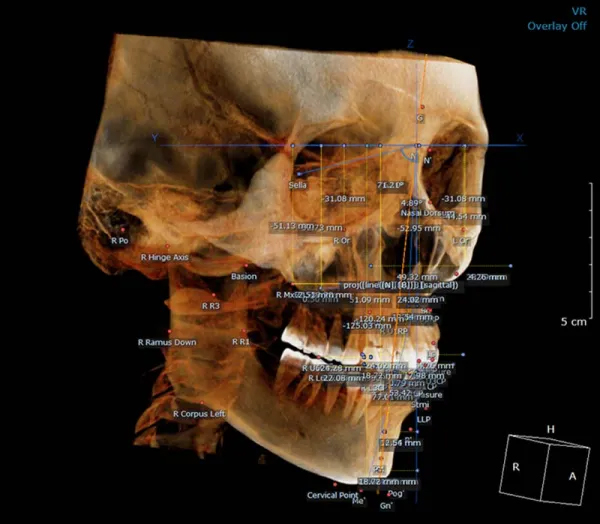

18×16.5 cm | Anterior View

18×16.5 cm | Airway Analysis

18×16.5 cm | 3D Cephalometric analysis